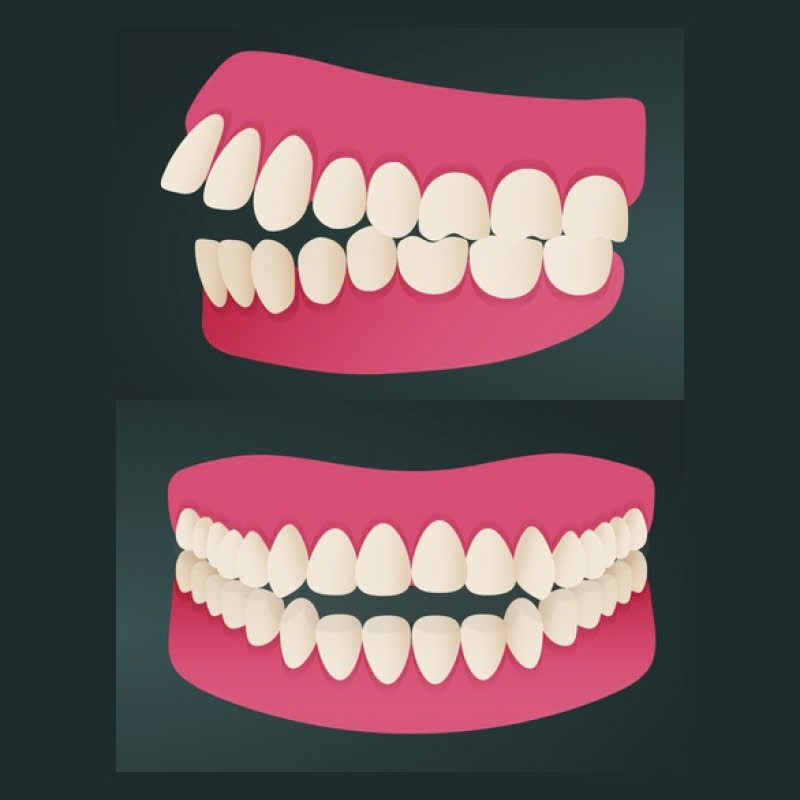

Điều chỉnh mài xương ổ răng, hay còn được gọi là phẫu thuật chỉnh hình xương hàm, là một kỹ thuật nha khoa sử dụng dụng cụ chuyên dụng để điều chỉnh kích thước và hình dạng của xương ổ răng, nhằm mục đích khắc phục các khuyết điểm về răng miệng. Thông thường, dịch vụ này được áp dụng cho các trường hợp răng hô, răng vẩu, cười hở lợi và xương hàm hô.

- Răng hô: Răng mọc chìa ra phía trước, tạo cảm giác hàm răng bị nhô ra.

- Răng vẩu: Răng mọc lệch ra ngoài, tạo cảm giác hàm răng bị loe ra.

- Cười hở lợi: Lợi bị lộ quá nhiều khi cười, ảnh hưởng đến thẩm mỹ.

- Xương hàm hô: Xương hàm trên hoặc hàm dưới bị nhô ra, tạo cảm giác mặt bị dài, thiếu cân đối.